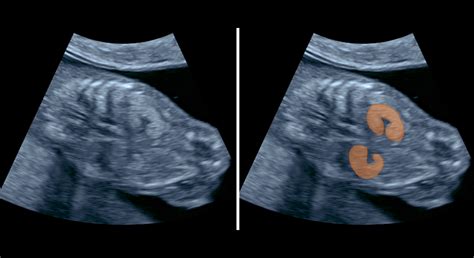

Pri prvom ultrazvukovom vyšetrení sa lekár sústredí na niekoľko kľúčových bodov. V prvom rade ide o potvrdenie početnosti tehotenstva, teda koľko plodov sa v maternici uchytilo. Plod sa v rámci prvého ultrazvuku zvykne merať za pomoci samotného ultrazvukového prístroja, pričom výsledky tohto merania môžu vo veľkej miere potvrdiť prítomnosť takmer 50 percent vrodených chýb a chorôb.

Samotné ultrazvukové vyšetrenie medzi 11+0 a 13+6 týždňom gravidity poskytuje množstvo informácií. V tomto období sa dajú pozorovať niektoré znaky (markery), ktoré môžu signalizovať závažné chromozomálne abnormality plodu (Downov syndróm, Edwardsov syndróm, Patauov syndróm, Turnerov syndróm a ďalšie). Rovnako tak sa dajú vidieť aj mnohé štrukturálne (morfologické) anomálie plodu (gastroschíza, omphalokéla, Cantrellova pentalógia, hrubé anomálie končatín, sirenomélia, anencephalia, acrania, atď.). Pri veľmi dobrých echogénnych podmienkach sa dajú dokonca detekovať aj niektoré, v tomto období väčšinou menej nápadné, anomálie srdca.

Najdôležitejšou meranou hodnotou pri ultrazvukovom vyšetrení je stanovenie hrúbky tekutiny v záhlaví plodu - nuchal translucency NT (šijové prejasnenie). Tekutinu v záhlaví má každý plod, rozhodujúca je hrúbka vrstvy tekutiny. Ďalším dôležitým parametrom pri ultrazvukovom vyšetrení je meranie prítomnosti/neprítomnosti nosovej kostičky (NB-nasal bone). Nosovú kostičku zobrazujeme pri vyšetrení profilu tváre plodu. Neprítomnosť nosovej kosti sa vyskytuje až v 70% u plodov s Downovým syndrómom.